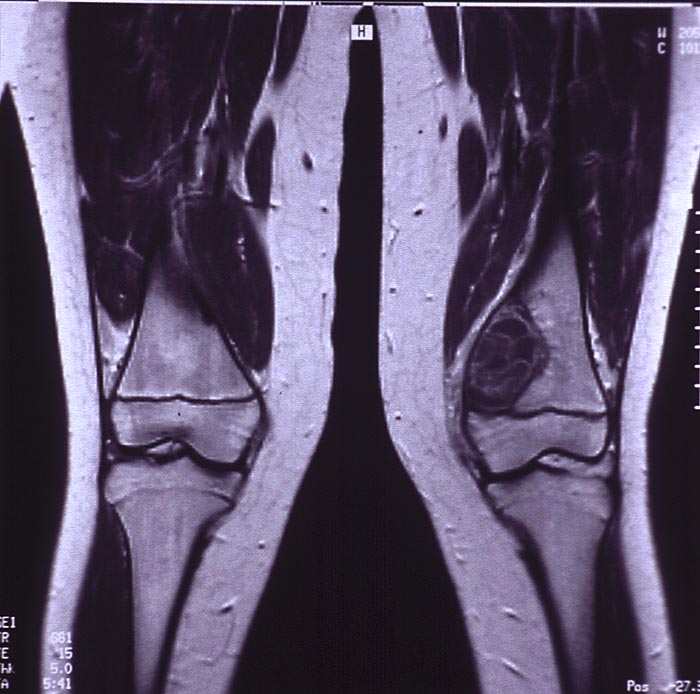

MRT: Radiologisch erkennt man in der distalen linken Femurmetaphyse medial eine exzentrisch gelegene mehrkammrige Osteolysezone proximal der offenen Epiphysenfuge.